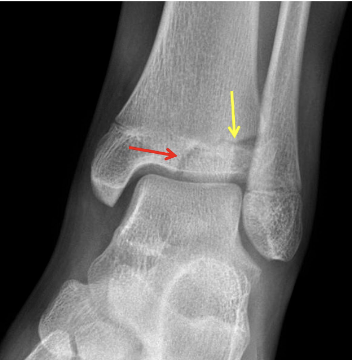

What type of fracture is this?

Trimalleolar

What is a trimalleolar fracture?

Fracture of ankle joint involving medial and lateral malleoli and posterior lip of distal tibia